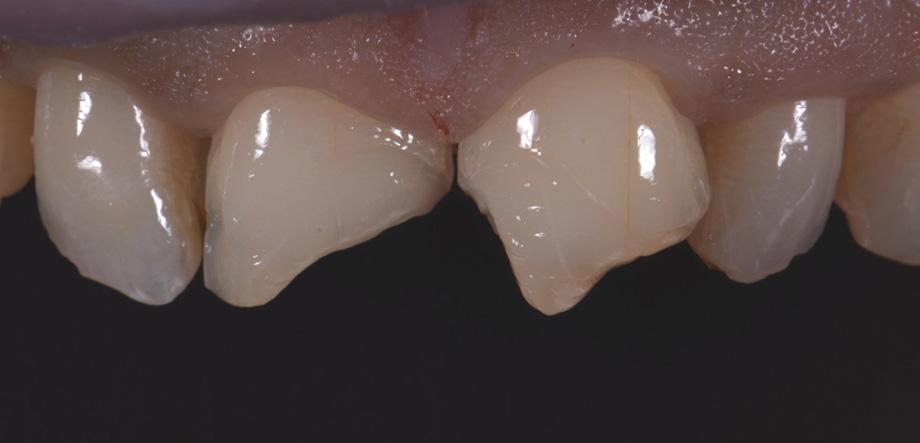

Fig. 3 Central incisors after removal of the old restorations and the beveling of the enamel.

During minimally invasive tooth preparation, bevels were created at the margins to provide for a smooth optical transition from the natural tooth structure to the composite.

An adhesive (CLEARFIL™ Universal Bond Quick) was applied after selective etching of the enamel to achieve a strong bond. With the aid of the silicon index, it was easy to create the palatal shells of the restorations with CLEARFIL MAJESTY™ ES-2 Premium in the shade A3E (enamel), which matches the determined tooth shade A3. The dentin core was built up with the same composite in the recommended shade A3D (dentin), mamelons were modelled and some CLEARFIL MAJESTY™ ES-2 Premium in the shade WD added for the incisal halo, while some individual effects (like enamel cracks) were imitated with brown stain. The build-up was finalized in the interproximal and labial areas with composite in the shade A3E. Between the central incisors, a wedge was used to retract the papilla and facilitate the designing of the interproximal contact area. The finished and pre-polished restorations already had a natural appearance.